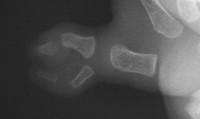

| Case 1. Wassell IV duplication of the proximal and distal phalanges, with characteristic deviation of the thumbs away from each other at the MCP and toward each other at the IP joints. This was corrected by metacarpal head narrowing, opposing closing wedge osteotomies of the metacarpal and proximal phalanx and collateral ligament reconstruction using parts from the deleted digit. |